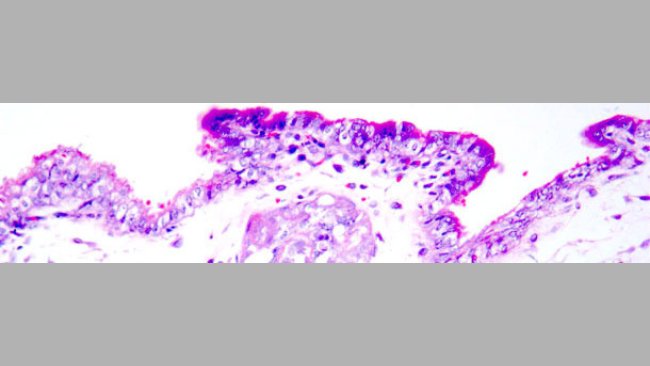

IA nelle scrofette con seme contaminato con PCV2. Protezione mediante vaccinazione delle scrofette contro il PCV2

La vaccinazione delle scrofette contro il PCV2, prima dell'inseminazione con seme infetto da PCV2, ha diminuito chiaramente la carica e l'escrezione virale, fino a valori compatibili con la protezione dei feti.